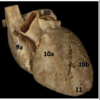

Identify the arteries

Identify #10a

Right venticle

Identify #10b

Left ventricle